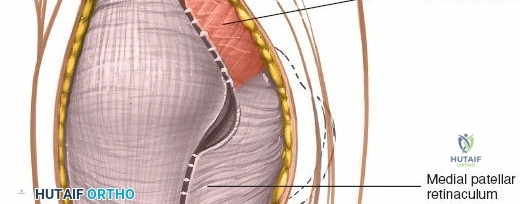

4. Medial Retinaculum:

This fascial layer provides static stability to the patella. It includes fibers from the vastus medialis, extending to the patella and patellar tendon. Key components include the medial patellofemoral ligament (MPFL), originating from the medial femoral epicondyle and inserting onto the superomedial patella, providing 50-60% of the resistance to lateral patellar displacement. The medial patellotibial ligament also contributes to medial stability. The arthrotomy incision typically passes through the medial retinaculum.

3. Medial Parapatellar Arthrotomy (Capsular Incision)

* It then follows the border between the vastus medialis obliquus (VMO) and the patella, curving distally along the medial border of the patella.

The medial retinaculum and vastus medialis obliquus are exposed. The proposed capsular incision along the medial patellar border is outlined.